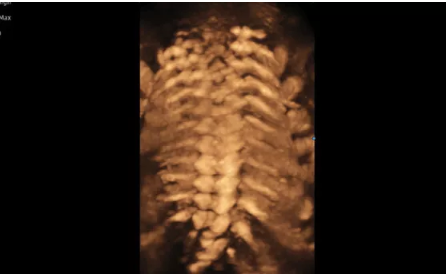

3D/4D成像方面,Hera i 10通過結(jié)合先進(jìn)的圖像渲染技術(shù),著重加強(qiáng)了邊緣和小結(jié)構(gòu)的可視化能力。